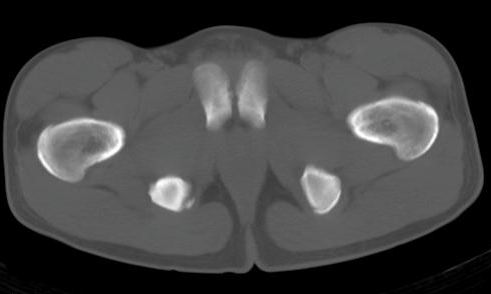

男性,15岁,半年前曾有做运动摔伤史,伤后左肢麻木,一天后恢复,两个月后因右臀部隐痛照片示右坐骨下骨性密度影,现复查见骨性影无明显改变。求助诊断!

坐骨撕脱骨折.

坐骨撕脱性骨折

坐骨结节骨折

坐骨粗大,有瘤骨,基地部有囊状骨缺损。不应为外伤史迷惑,应考虑外生软骨瘤病或骨膜硬纤维瘤。请勿见笑。

坐骨撕脱性骨折伴骨化性肌炎

如果是撕脱骨折,应该有疼痛,而病史是伤后左肢麻木,一天后恢复,两个月后因右臀部隐痛才就诊,病变在肌肉区,故考虑骨化性肌炎

坐骨陈旧性撕脱性粉碎性骨折伴骨痂形成.